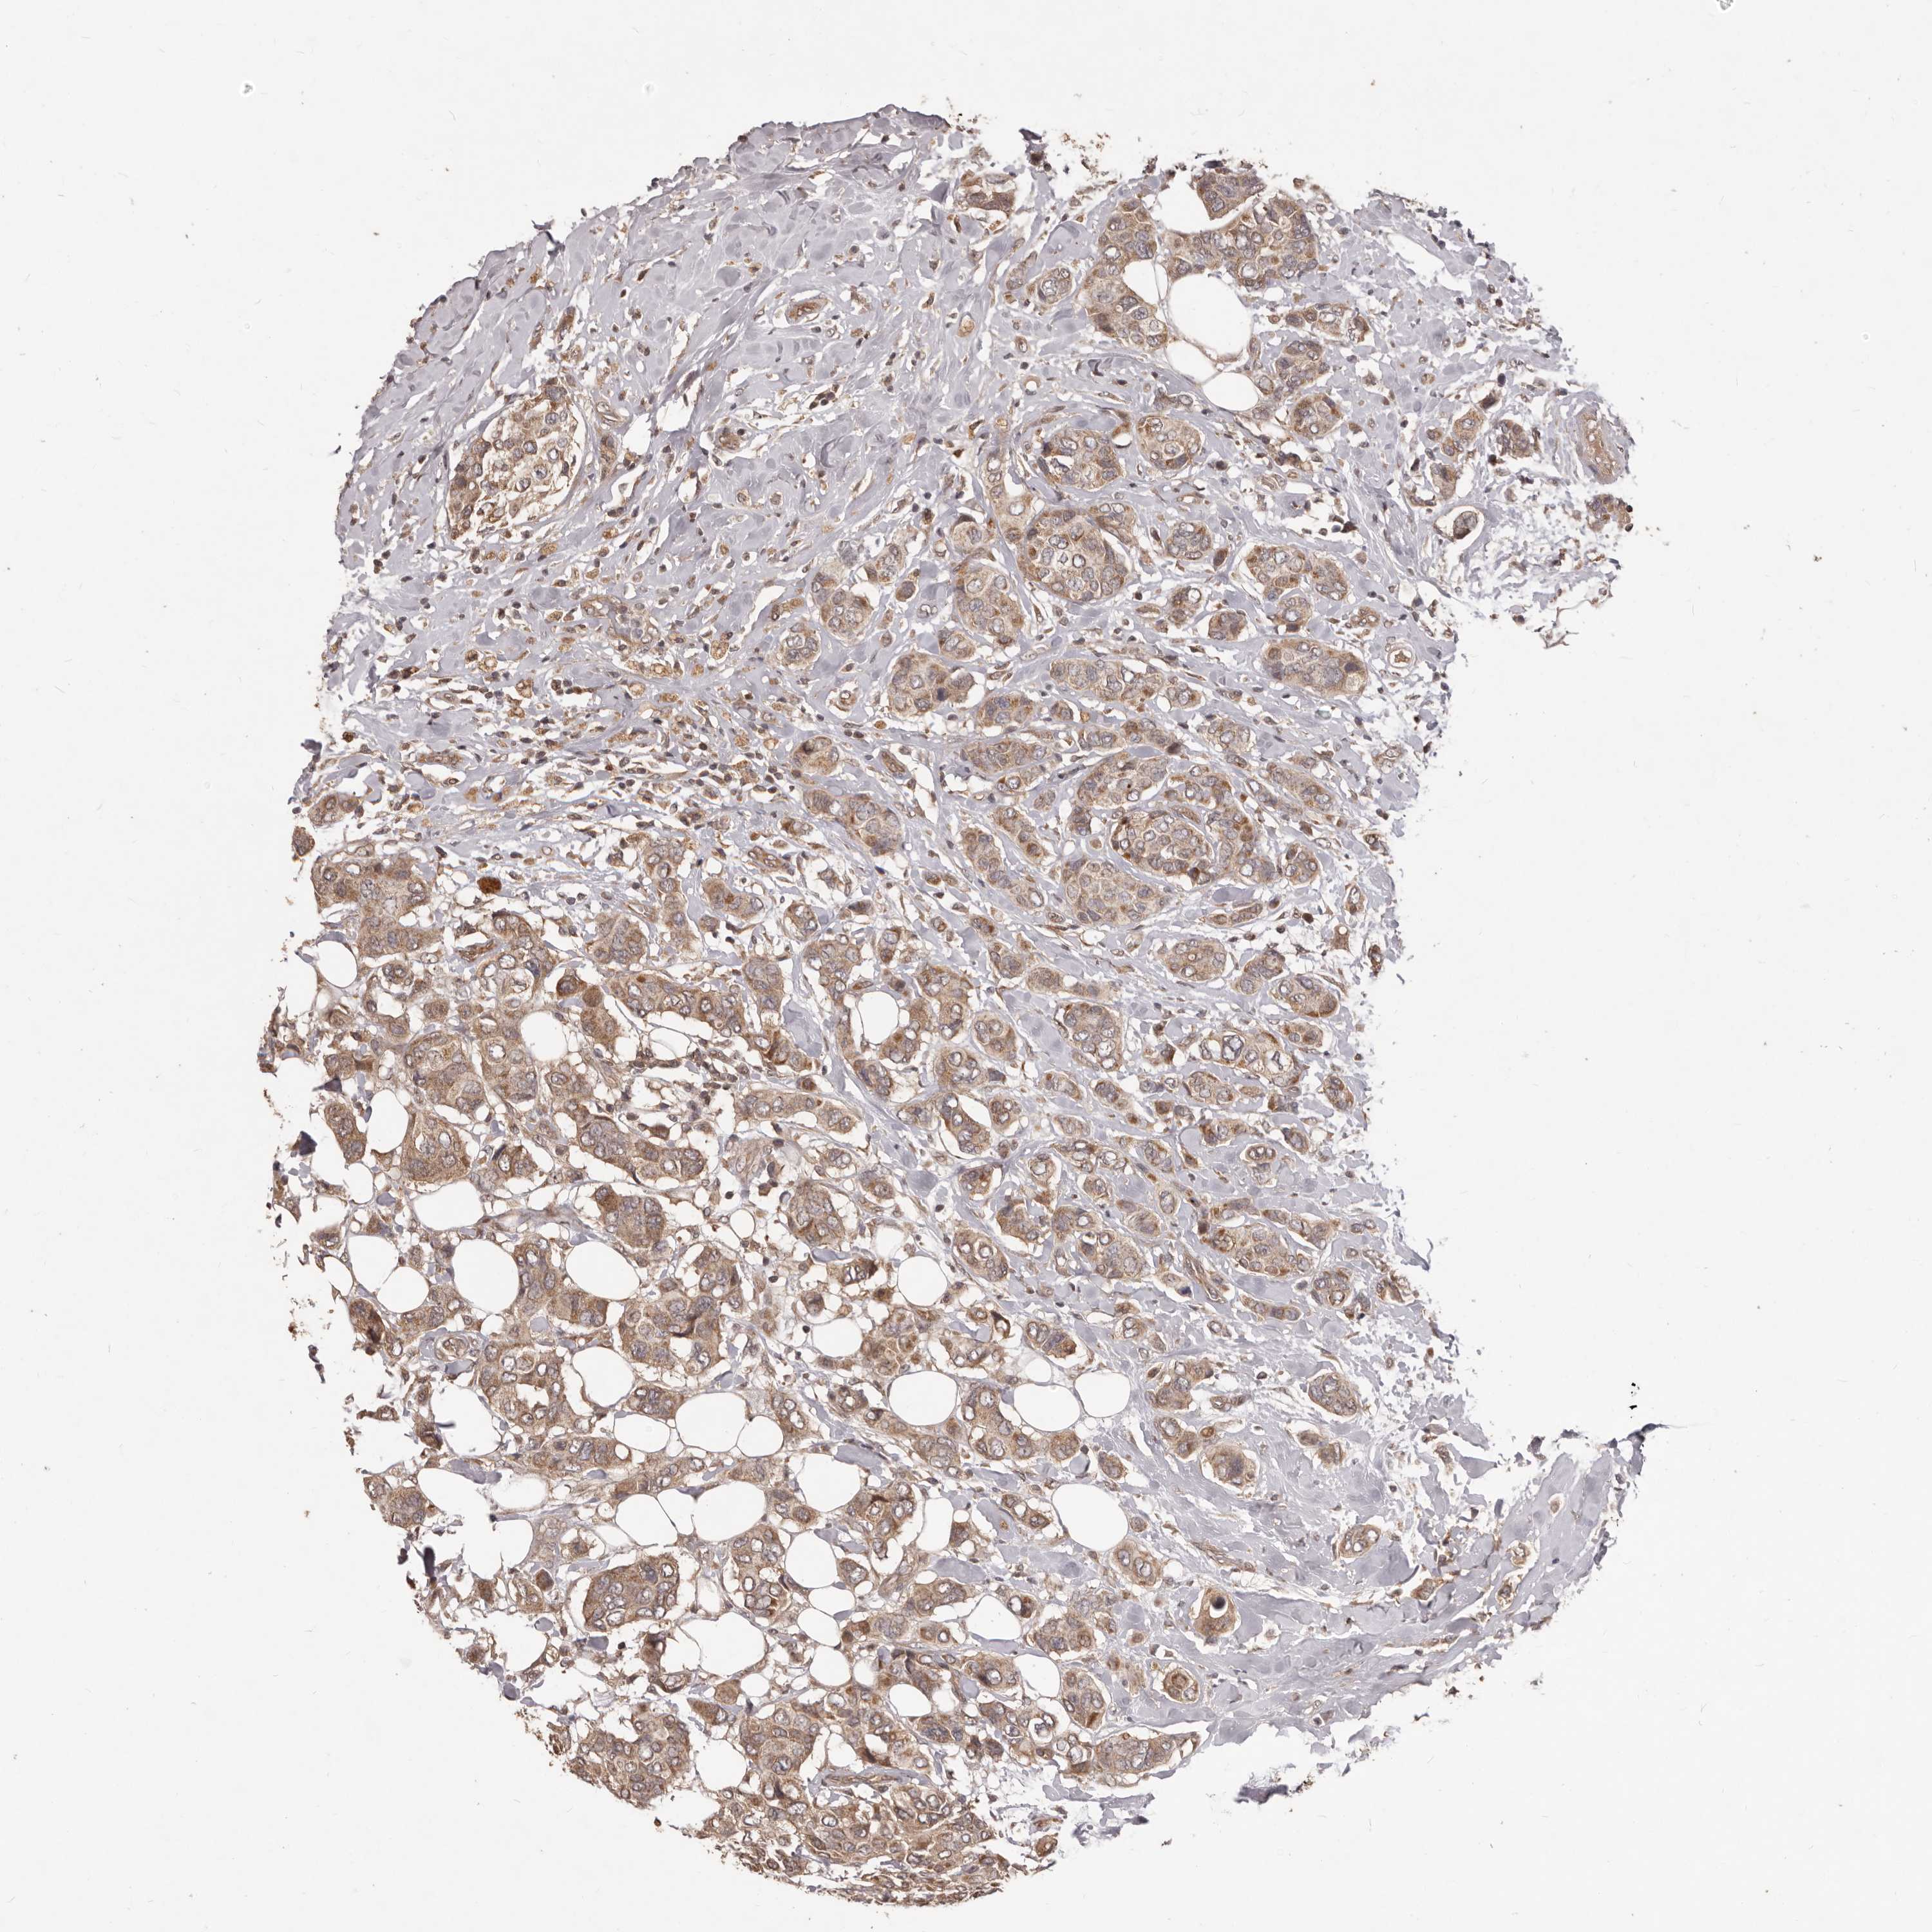

CANCER BREAST CANCER Show tissue menu

BRCA TCGA BRCA VALIDATION PROTEIN EXPRESSION

ANTIBODIES

AND

VALIDATION